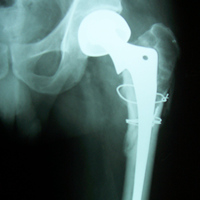

Case:14 Periprosthetic Fracture

60 years old patient with total knee replacement on left knee presented with open grade 1 injury. Debridement & slab given on emergency bases. Fixation with plate & screws done. Union was seen after 6 months.

Pre-Op AP

Pre-Op Lat.

Immdiate Post-op

1 and half months Post-op

2 and half months Post-op

3 and half months Post-op

4 and half months Lateral

6 Years Follow-Up